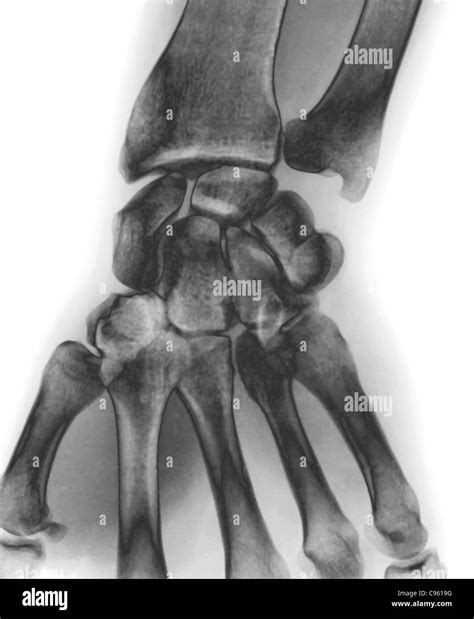

A wrist X-ray is a non-invasive diagnostic test that uses a small, controlled amount of ionizing radiation to produce images of the internal structures of the wrist. When a radiologist or physician reviews these images and finds no fractures, dislocations, or significant bony abnormalities, they classify the report as a normal wrist X-ray.

This imaging modality focuses primarily on the dense tissues within the body, specifically the bones. The wrist is a complex joint composed of eight carpal bones, the distal ends of the radius and ulna (the bones of the forearm), and the metacarpals (the bones of the hand). A high-quality X-ray provides a clear visualization of these structures, allowing medical professionals to check for alignment, bone density, and integrity.

To understand what constitutes a normal wrist X-ray, it is helpful to know what the radiologist is looking for. The anatomy visualized includes several critical components:

Anatomic Structure Purpose of Inspection

Distal Radius & Ulna Checking for fractures near the joint surface.

Carpal Bones Ensuring no small bone fractures (e.g., Scaphoid).

Joint Spaces Looking for uniform gaps between bones (signs of arthritis).

Alignment Confirming that bones are in their correct anatomical position.